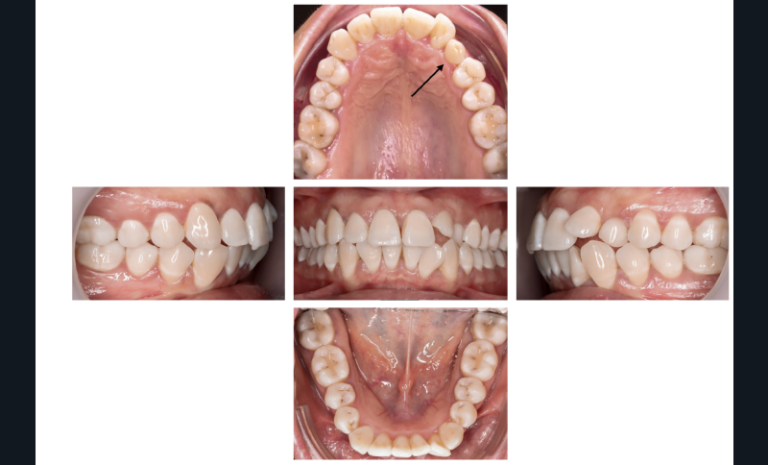

Dans l’exemple (fig. 1 et 2), la patiente présente une classe 1 molaire et classe 2 canine bilatérale sur un schéma normodivergent de classe 2 squelettique associé à une biproversion incisive et la canine 23 incluse.

Avec les aligneurs que je programme, la première phase de traitement consiste en un stripping de 0,5 mm de mésial molaire à distal canine afin de permettre une distalisation des prémolaires et canines pour obtenir un gain possible de 1,5 mm en mésial des canines avant l’étape d’alignement incisif.

Ces obstacles sont automatiquement supprimés grâce à cet ancrage naturel lié à la conception et à la programmation des aligneurs (fig. 3) :

- sur les quatorze dents de l’arcade, seules les prémolaires et canines sont mises en mouvement ;

- toutes les autres dents ne sont pas déplacées et n’ont pas été déplacées préalablement, donc la réaction histologique du déplacement dentaire n’est pas amorcée sur ces huit dents d’ancrage ;

- chaque prémolaire et canine est encapsulée dans son logement sur l’aligneur et prévient tout risque de récidive mésiale ;

- l’ensemble des prémolaires et canines est sollicité en un seul temps, avec une seule série d’aligneurs, ce qui permet de réduire la durée clinique de la phase de distalisation des secteurs latéraux.